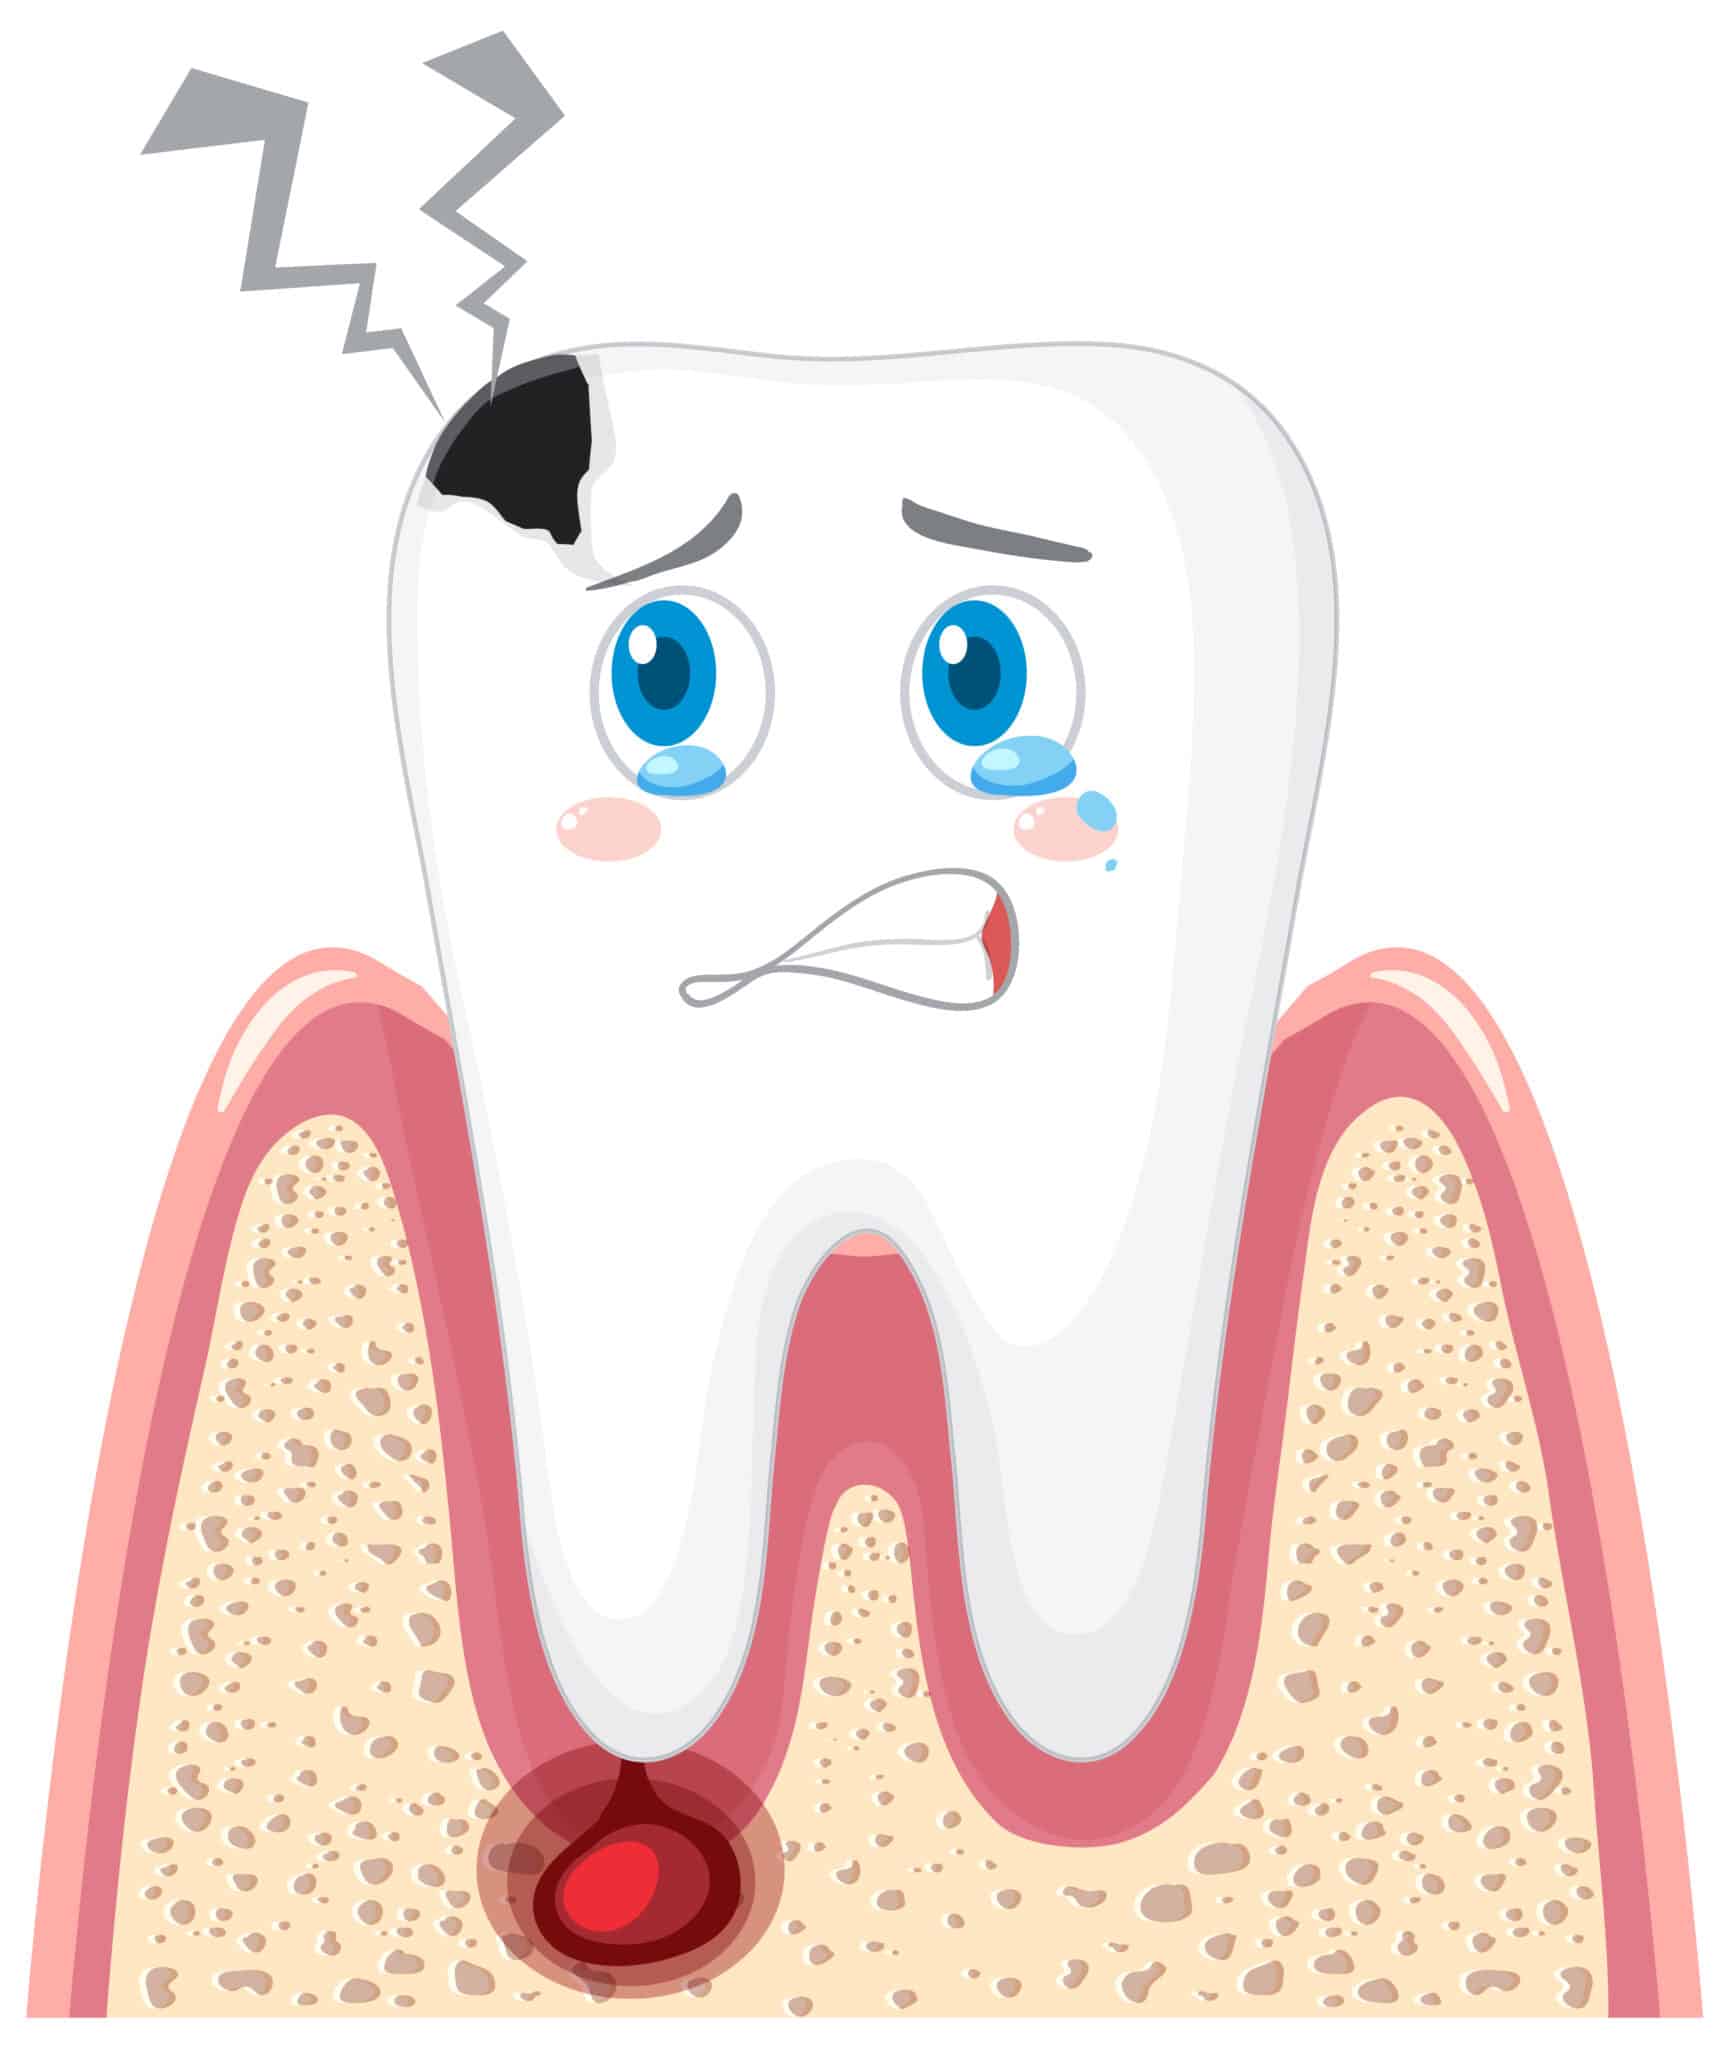

La caries es uno de los problemas dentales más comunes, pero cuando aparece varias veces en el mismo diente o en zonas cercanas hablamos de caries recurrente. Muchas personas se sorprenden cuando, después de haberse realizado un empaste, el problema vuelve a surgir meses o incluso años después. Esto no siempre significa que el tratamiento anterior haya fallado, sino que existen diferentes factores que pueden favorecer la reaparición de la caries.

La caries recurrente aparece cuando una lesión cariosa se desarrolla en el mismo lugar donde ya se había realizado un empaste o muy cerca de él. Esto puede ocurrir porque pequeñas bacterias vuelven a acumularse en esa zona y empiezan a debilitar nuevamente el esmalte.

En muchos casos, el paciente no nota ningún síntoma al principio. La caries puede avanzar lentamente bajo el empaste o alrededor de él, y solo se detecta durante una revisión dental. Por eso los controles periódicos son fundamentales para mantener la salud bucal.

Cuando no se detecta a tiempo, la caries puede avanzar hasta el interior del diente. En esos casos, el dentista puede recomendar tratamientos más complejos como una reconstrucción más amplia o incluso una [endodoncia: cómo salvar tu diente con un tratamiento de conductos].